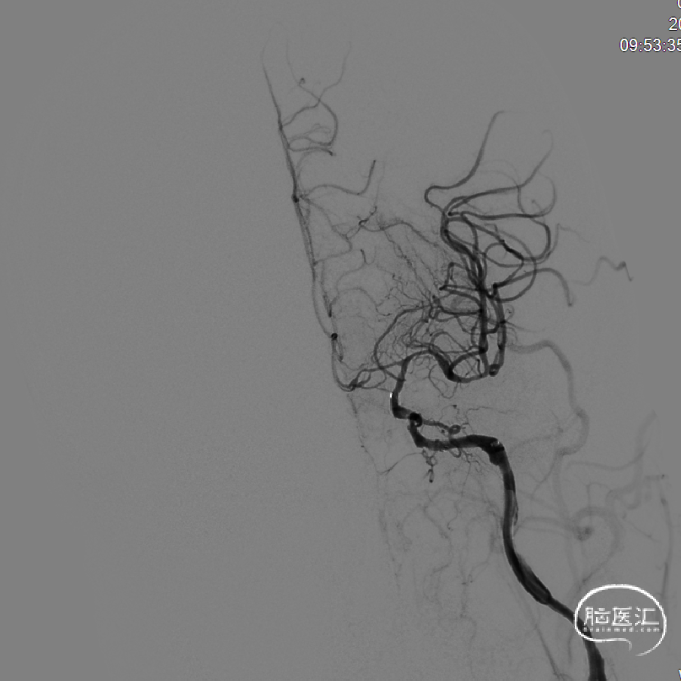

术前DSA:左侧颈内动脉起始段闭塞,可见残端,左侧颈外动脉经眼动脉向左侧颈内动脉供血区部分代偿,可见逆流至海绵窦段,左侧大脑后动脉经软脑膜向左侧大脑中动脉供血区代偿;右侧颈内动脉起始部中度狭窄(40%);右侧椎动脉开口重度狭窄(70%);右侧锁骨下动脉肋颈干开口以远处轻度狭窄;左椎动脉开口中度狭窄。

建立通路:造影证实左侧颈内动脉闭塞,可见残端,动脉晚期可见颈外动脉经眼动向大脑中动脉代偿供血,并逆流至海绵窦段。